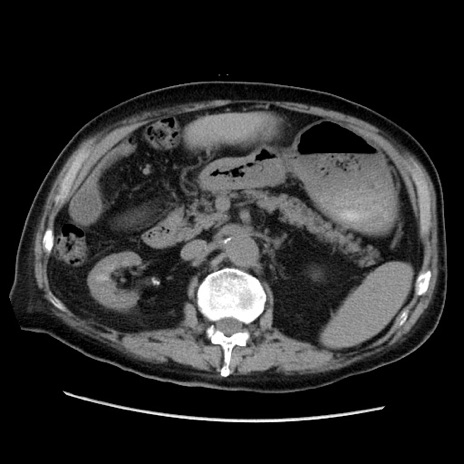

症例21(横断像)

【症例】70歳代男性

【主訴】腹痛

【現病歴】肝硬変・肝細胞癌にてかかりつけの方。約9時間前に食後より腹痛出現。症状が徐々に増悪し、嘔吐出現したため来院。

【既往歴】肝硬変、肝細胞癌(RFA、TACE後)

【身体所見】意識清明、表情苦悶様、BT 36℃、BP 129/78mmHg、P 88bpm、SpO2 97%(RA)、右上腹部から心窩部にかけて圧痛あり、反跳痛なし、筋性防御あり。

【データ】WBC 5800、CRP 0.16